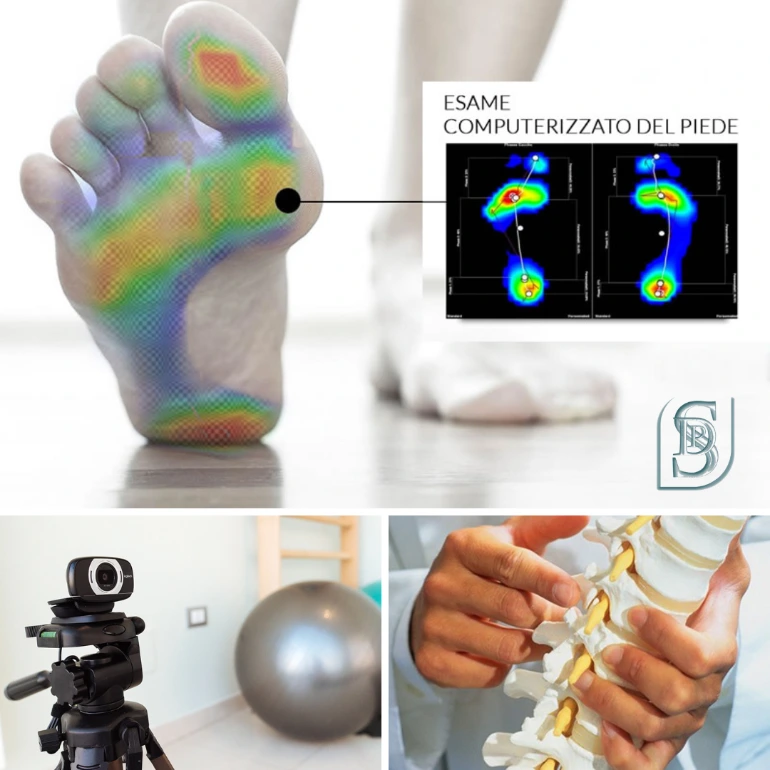

Esame baropodometrico

Lo strumento fondamentale utilizzato in Ergonomia Posturale è il baropodometro (con protocollo Biomeccanico, Antropometrico, Ergonomico) il quale offre immagini pressorie, rappresentanti le percentuali del peso nelle varie aree del piede (unico e fondamentale punto fisso di relazione dell'ambiente esterno con il nostro sistema di equilibrio), e immagini relative al centro di gravità.

Esame Fotografico della postura

L'esame fotografico della postura è un metodo di ricerca ed elaborazione dell'immagine fotografica nell'analisi posturale. La ripresa di immagini in tempo reale tramite apposita webcam, facilita e velocizza la fase di osservazione.